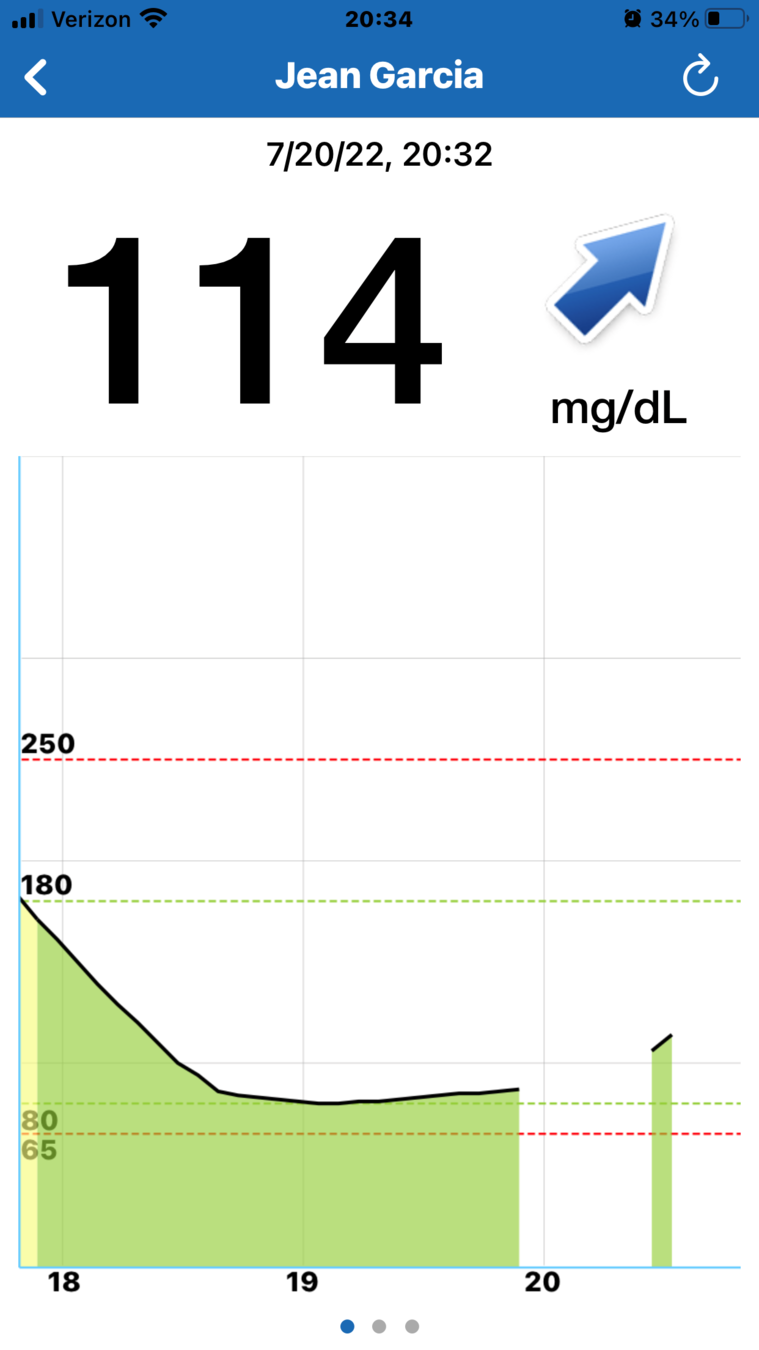

Cuando abre la aplicación para móvil Eversense®,

se muestran principalmente su nivel

de glucosa actual y una flecha de tendencia.

Y, en la parte inferior, se encuentra el gráfico de tendencia de la glucosa.

Las líneas discontinuas rojas indican los niveles de alerta de glucosa alta y baja, y las líneas discontinuas verdes indican el intervalo objetivo.

Todos los eventos que introduzca en la aplicación (como una calibración, comida, ejercicio

o insulina) o las alertas que reciba, se mostrarán en el gráfico de tendencia con un icono.

Con la MCG, puede ver de un solo vistazo:

- cuál es su nivel de glucosa en sangre;

- hacia dónde se dirige y con qué rapidez

- y las últimas 3 horas de datos de glucosa.

La flecha de tendencia es una ventaja especialmente importante de la MCG.

Le permite anticiparse a su nivel de glucosa futuro y adaptar de forma preventiva sus decisiones sobre el tratamiento de la diabetes según sea necesario.

Los distintos ángulos de la flecha hacen referencia a una velocidad de cambio distinta, como se muestra en el gráfico de la derecha:

- estable;

- aumentando moderadamente;

- descendiendo moderadamente;

- aumentando con mucha rapidez;

- y descendiendo con mucha rapidez.